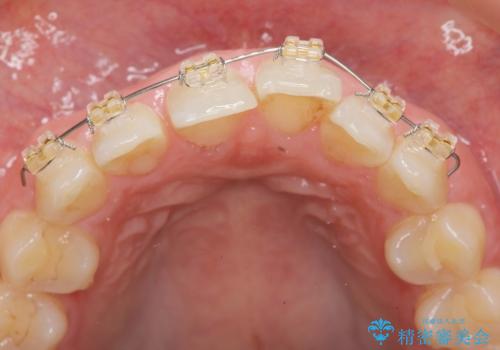

前歯のガタつきをきれいに マウスピース矯正治療

- 「前歯のガタつきをきれいにしたい。」と矯正治療を希望され来院されました。

前歯のガタつきをワイヤー部分矯正、上顎前突の咬合関係を後方移動することで理想的な咬合関係を確立します。

上顎の全体的な後方移動を実現するためにマイクロインプラントを併用したゴムかけを行ったことで理想的な咬合関係を確立することができました。